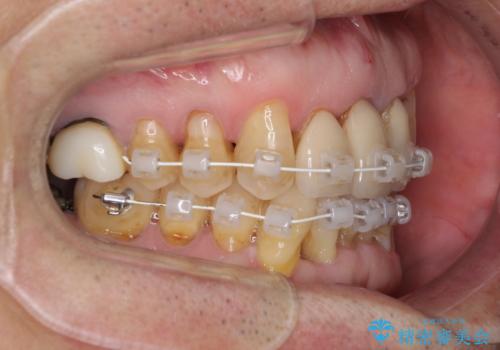

また、前歯の部分矯正も希望されたため、歯周外科処置と平行して矯正治療を行うこととしました。

患者様ご自身が痛みには強いとおっしゃっていたので、治療中は特に辛いと感じることはなく進めることができました。